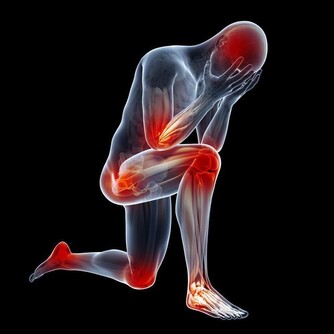

第三類:骨質疏鬆導致腰痛

中老年女性,特別是絕經後的女性,由於脊柱的骨量減少,脊柱承重能力隨之降低,機體在負重甚至行走中也會出現腰背部疼痛。

50%以上的骨質疏鬆患者會出現疼痛的症狀,且腰椎和髖部都是最早發生骨質疏鬆的部位,所以很多骨質疏鬆的患者,在患病初期都會腰痛的症狀。